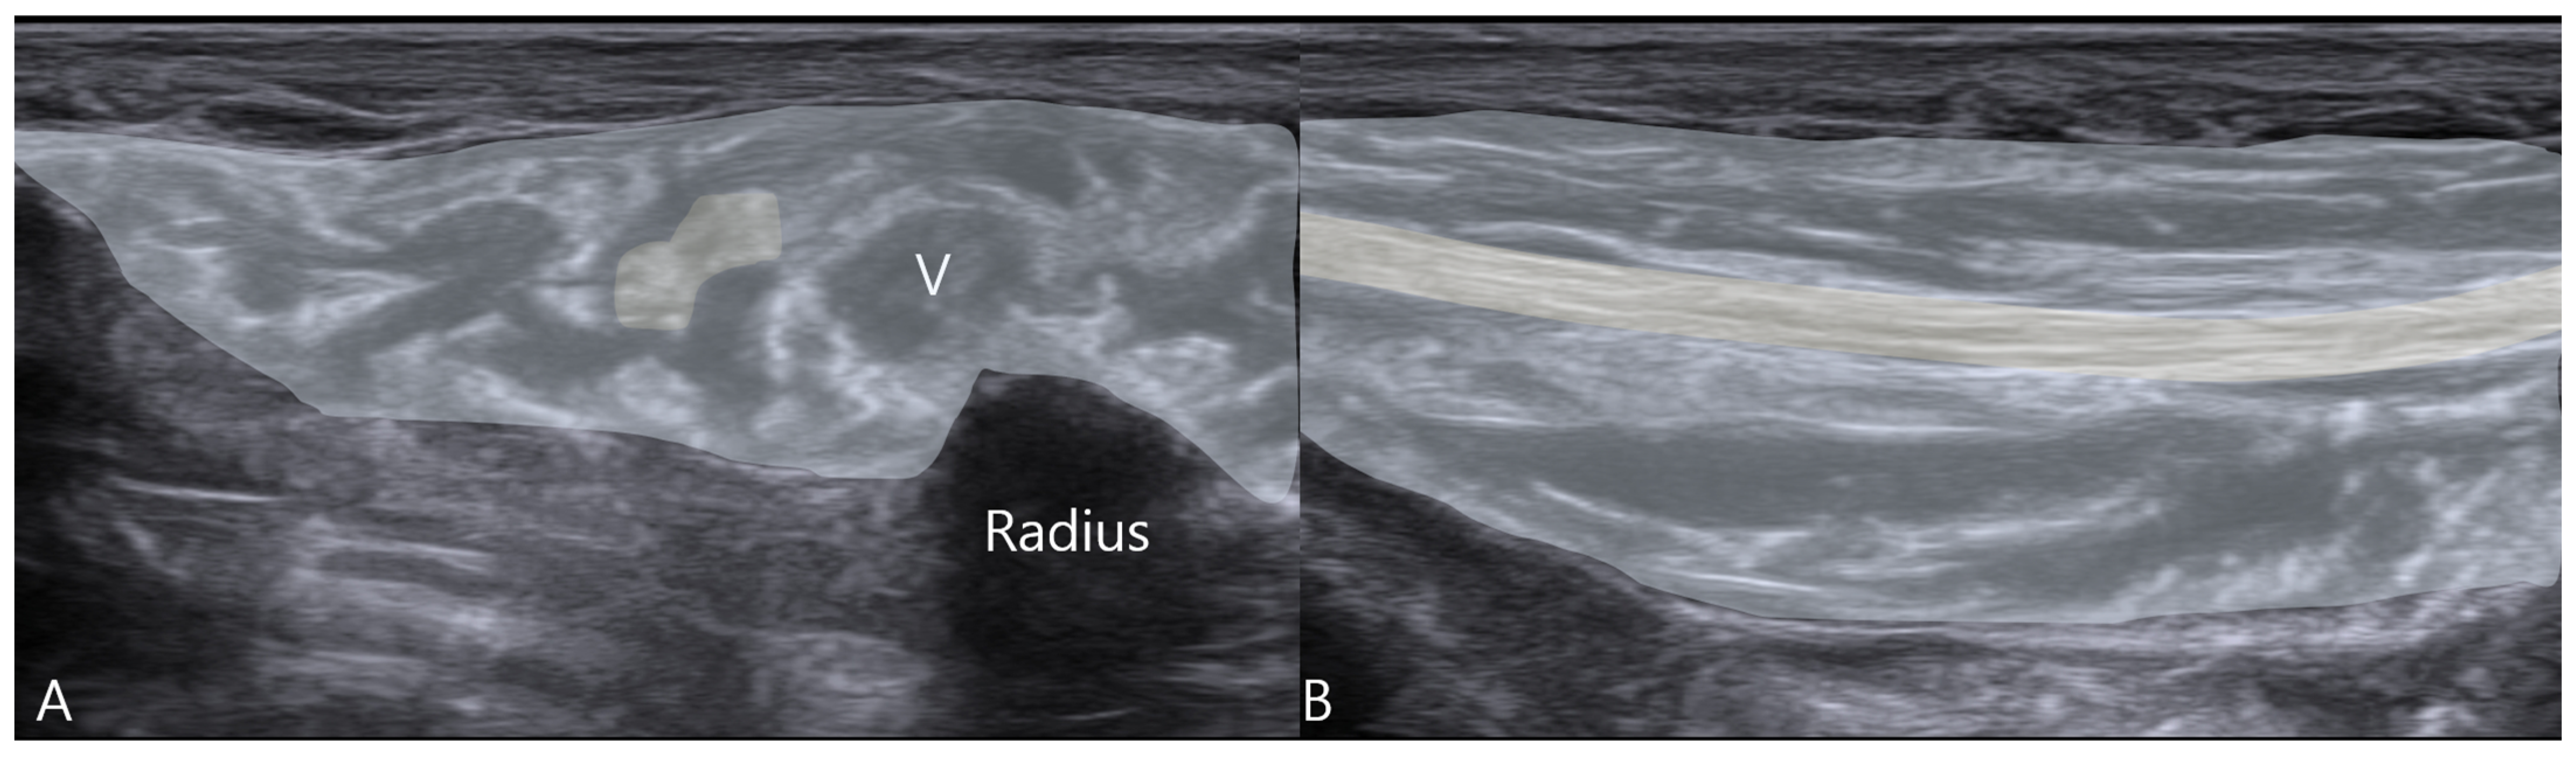

2.4. Therapeutic Intervention

- Mechanical Neurolysis: The injected fluid creates a physical separation between the nerve and the surrounding constrictive tissues, lysing adhesions and effectively expanding the perineural space. This immediately alleviates mechanical compression and restores normal nerve gliding, as evidenced by the resolution of snapping on follow-up ultrasound.

- Neuromodulatory Effects of Dextrose: The use of 5% dextrose, rather than saline or local anesthetics, adds a therapeutic pharmacological dimension. Prolotherapy theories and emerging evidence suggest that dextrose acts as a mild irritant that may stimulate healing and have neuromodulatory properties. It is postulated to stabilize neuronal membranes, reduce ectopic discharges, and modulate pain receptors like TRPV1, thereby reducing neurogenic inflammation and pain signaling [31,32,33,34]. Randomized trials in carpal tunnel syndrome have shown superior outcomes with dextrose hydrodissection compared to saline, supporting its bioactive role [29].